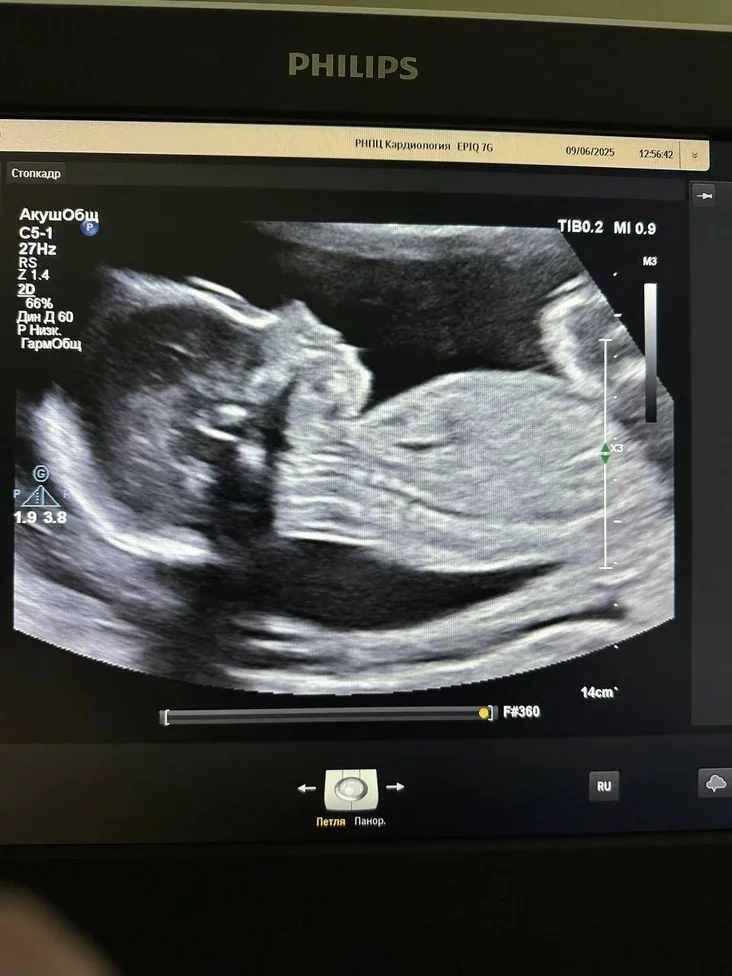

Jak rastłumačyli ŭ viedamstvie, heta była pieršaja takaja apieracyja ŭ historyi biełaruskaj miedycyny. U červieni 2025 hoda, kali dziciaci było tolki 23 tydni ad začaćcia, daktary znajšli ŭ levym pieradserdzi žančyny mijaksomu — dabrajakasnuju puchlinu, jakaja mahła vyklikać trombaembaliju, insult abo infarkt i pahražała žyćciu i maci, i dziciaci.

Kab vydalić utvareńnie, śpiecyjalisty praviali składanuju apieracyju na adkrytym sercy z vykarystańniem štučnaha krovazvarotu. Dziakujučy zładžanaj pracy kamandy z RNPC «Kardyjałohija» i RNPC «Maci i dzicia» na 23‑m tydni ciažarnaści pahroźlivuju situacyju ŭdałosia paśpiachova vyrašyć. Apieracyju pravodziŭ kardyjachirurh Jaŭhien Kaściukovič.

Pa infarmacyi Ministerstva achovy zdaroŭja, apieracyja i paślaapieracyjny pieryjad prajšli biez uskładnieńniaŭ. Žančyna biaśpiečna danasiła ciažarnaść da 38 tydniaŭ. 2 kastryčnika joj zrabili płanavanaje kiesarava siačeńnie, i na śviet źjaviŭsia zdarovy chłopčyk vahoj 3230 hramaŭ i rostam 52 santymietry.